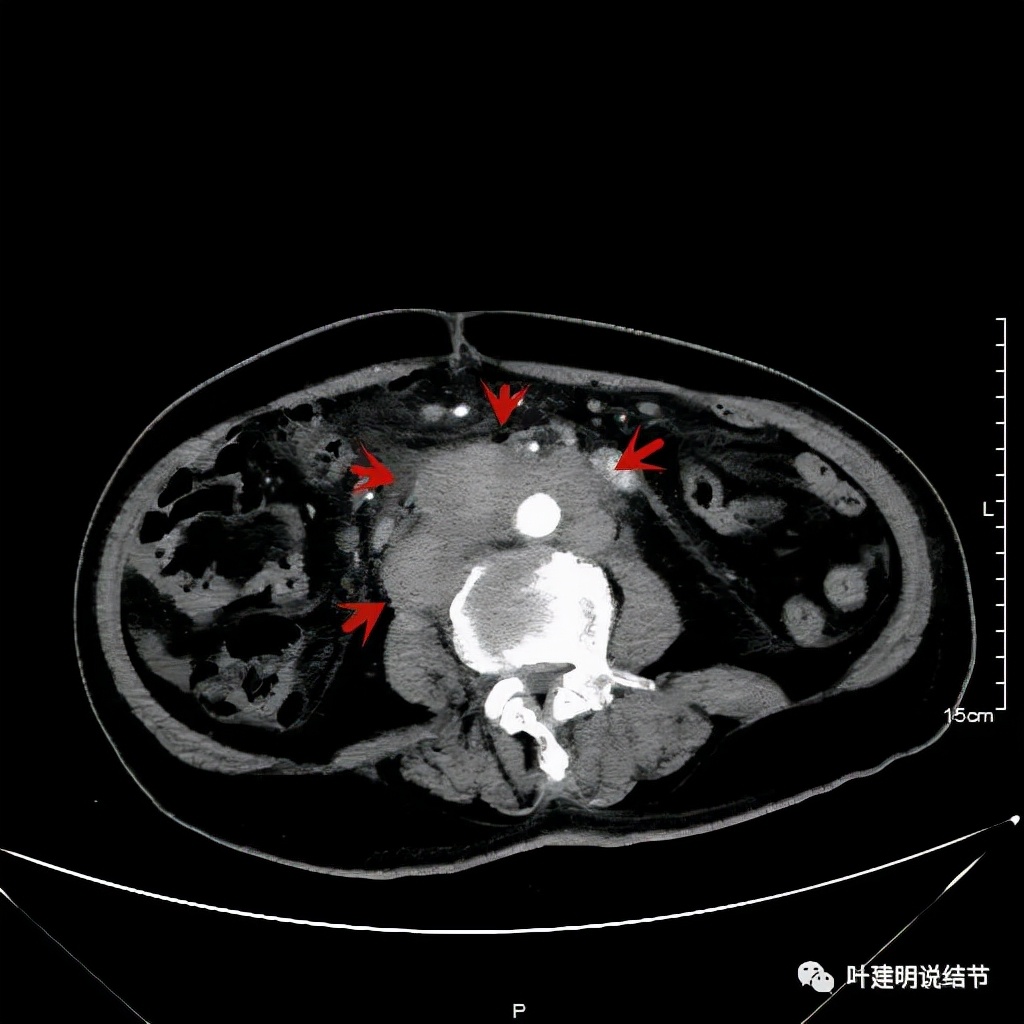

其实胸部CT示食管的病变感觉并不厉害,外侵或纵隔内转移均不明显,但其腹部的CT让人大吃一惊!

上图是初发现时的CT影像报告,其他CT图像上红色箭头所指范围内都是肿瘤,整合成团,挤压血管以及正常器官结构。你有见过原发灶这么不显眼,而腹部转移灶这么厉害的食管癌吗?但经过穿刺证实是转移性鳞癌,结合病史考虑是食管癌转移。手术自然是不可能了根治了,放疗也不合适,经过MDT并与患方充分沟通,依据食管癌治疗指南: